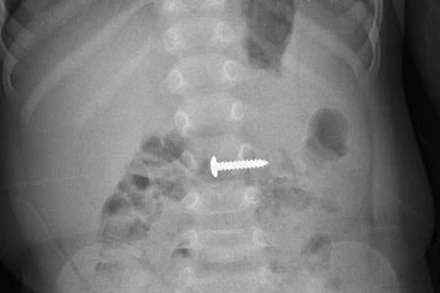

Thiết bị nội soi của Bệnh viện Sản-Nhi Cà Mau giúp phát hiện dị vật trong cơ thể của trẻ. (Ảnh do bệnh viện cung cấp)

Chiều 9/1, bác sĩ chuyên khoa II Trương Minh Kiển, Phó Giám đốc phụ trách điều hành Bệnh viện Sản-Nhi Cà Mau, cho biết, ê-kíp chuyên môn của bệnh viện vừa xử trí thành công 2 trường hợp bệnh nhi nhập viện nguy kịch do nuốt phải dị vật: trẻ bị thủng tá tràng và trẻ bị kim tây đâm sát động mạch chủ, đe dọa trực tiếp đến tính mạng.